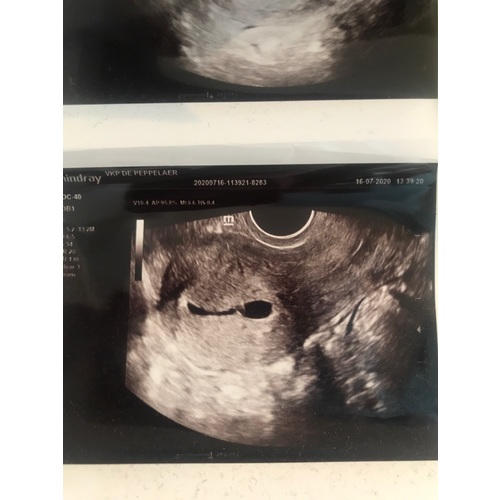

6 weken echo van mijn 2e zoontje.